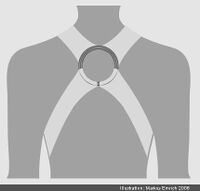

In den meisten Fällen wird nach der Bruchversorgung für mehrere Wochen ein Rucksackverband angelegt. Krankengymnastische Übungen unterstützen die Heilung. Die Sportfähigkeit ist erst nach Ausheilung des Bruches und Beschwerdefreiheit gegeben.

Eine Operation erfolgt meist nur bei besonderen Bruchformen.